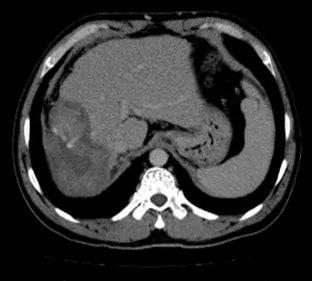

1. 肝脏原发病灶治疗前后磁共振扫描结果对比

淫羊藿素软胶囊治疗3、6、16、18个月后,肝脏病变呈现消融后改变,未观察到病灶进展。

治疗前

治疗3个月

治疗6个月

治疗16个月

治疗18个月